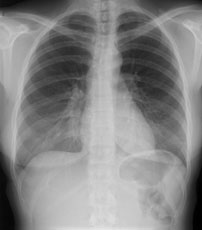

Eine 36-jährige Patientin kommt zu Ihnen in die Praxis. Sie berichtet über einen grippalen, fieberhaften Infekt, seit einer Woche bestehend.

In der Lungenauskultation sind Rasselgeräusche beidseits basal zu hören. Bei einem CRP von 160 mg/l veranlassen Sie ein Thoraxröntgen mit der Frage nach Infiltrat.

Hier sehen Sie die Bilder:

Thorax pa

Bild vergrössern